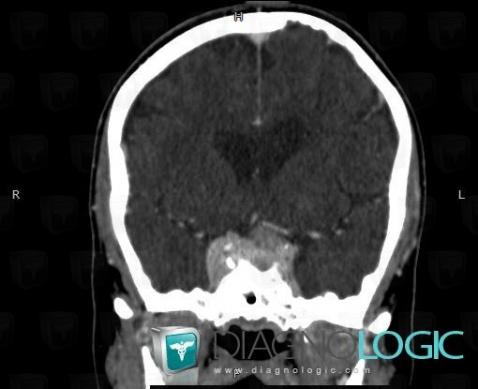

Méningiome , Hémisphères cérébraux, Scanner

Voici les informations spécifiques à l'image clé ci dessus:

- Diagnostic Méningiome , Localisation(s) Hémisphères cérébraux, comportant les gammes Lésion intracérébrale à réhaussement intense